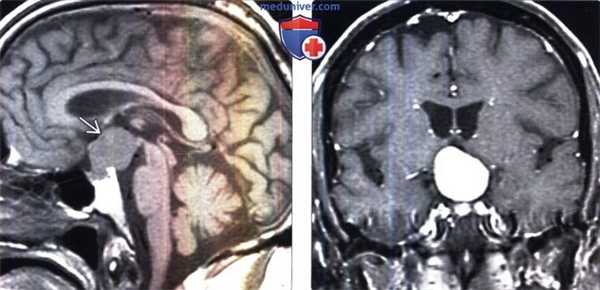

(Слева) Сагиттальный срез: питуицитома, поражающая ножку гипофиза и нейрогипофиз. Дольчатое супраселлярное объемное образование без значимой компрессии смежных структур — характерные признаки этого редкого веретеноклеточного глиального новообразования низкой степени злокачественности.

(Справа) Микропрепарат, окраска гематоксилином и эозином: типичные доброкачественные признаки питуицитомы: биполярные веретенообразные клетки с обильной эозинофильной цитоплазмой. Ядерная атипия и митозы отсутствуют. При иммуногистохимическом исследовании на GFAP наблюдалось интенсивное окрашивание, указывающее на астроцитарное происхождение опухоли. (Слева) МРТ, Т1-ВИ, сагиттальный срез: супраселлярное объемное образование с четкими контурами распространяющееся в задние отделы седла. Обратите внимание на отсутствие нормального «яркого пятна» гипофиза, что часто наблюдается при питуицитоме.

(Справа) МРТ, постконтрастное Т1-ВИ, корональный срез: у этого же пациента отмечается интенсивное однородное контрастное усиление данной крупной питуицитомы. Такой характер накопления контраста характерен для этоих редких опухолей нейрогипофиза или воронки. Эти хорошо васкуляризированные образования относятся к опухолям I степени злокачественности.

(Слева) МРТ, Т1-ВИ, сагиттальный срез: супраселлярное объемное образование с четкими контурами распространяющееся в задние отделы седла. Обратите внимание на отсутствие нормального «яркого пятна» гипофиза, что часто наблюдается при питуицитоме.